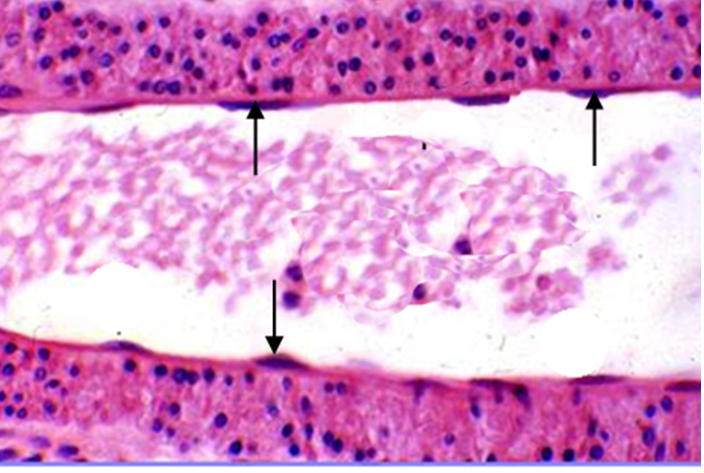

7.变移上皮transitional epithelium) 又称移行上皮,衬贴在排尿管道的腔面。由表层细胞中层细胞和基底细胞组成一个表层细胞可覆盖几个深层细胞,名盖细胞,有的细胞含两个细胞核。基底层细胞为矮柱状或立方形,胞质丰富。上皮的细胞形状和层数可随所在器官的收缩与扩张而发生变化。如膀胱空虚时,上皮变厚,细胞层数较多;当膀胱充盈时,上皮变薄,细胞层数减少,盖细胞变扁(图2-6)。

图2-6A 变移上皮模式图

2-6B  膀胱变移上皮(膀胱空虚) 2-6C  膀胱变移上皮(膀胱充盈)

图2-6 变移上皮